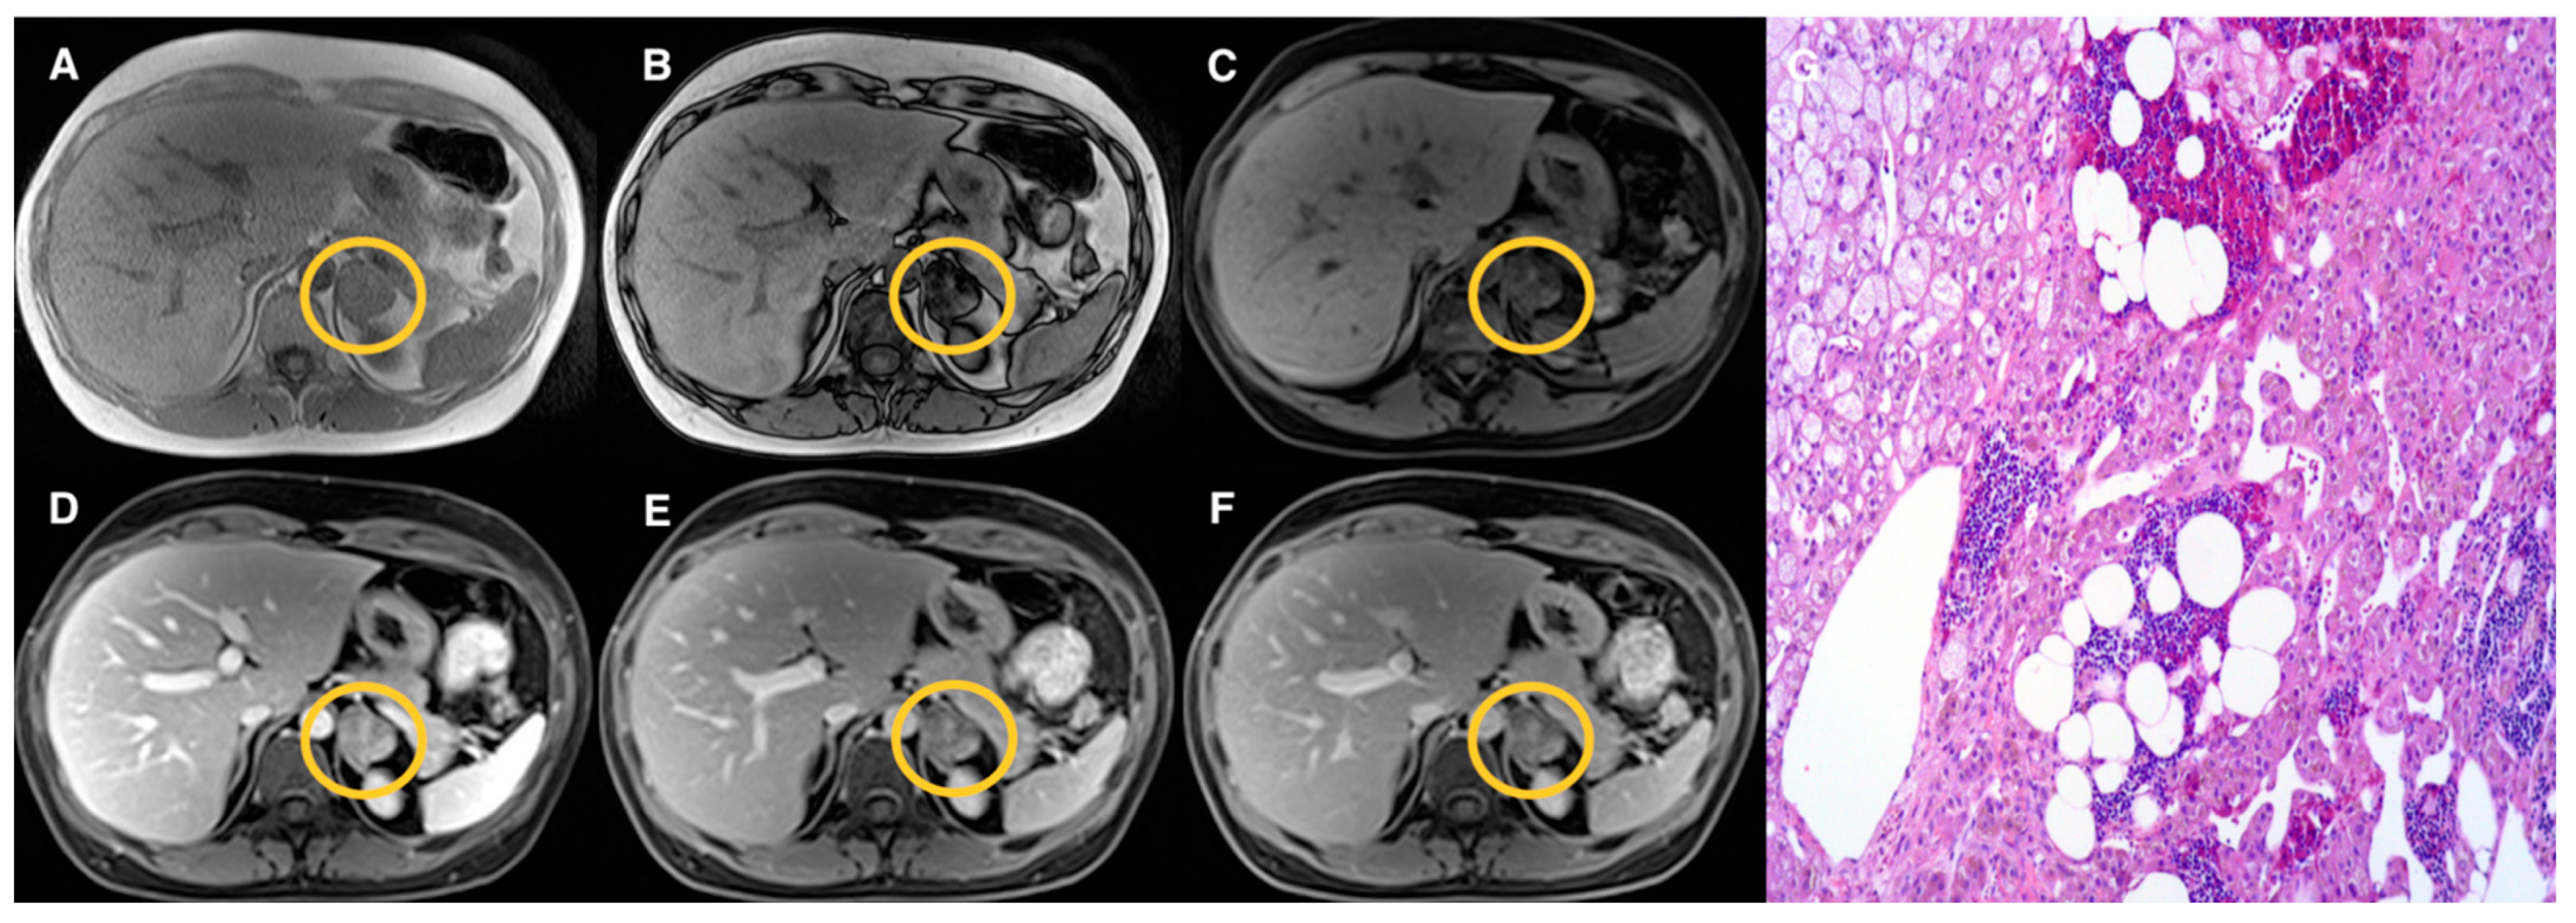

| Groups | Qualitative CS Signal Drop | Lesion Type | Total |

|---|---|---|---|

| 1 | Homogeneous | Adenomas (n = 19) | 19 |

| 2 | Heterogeneous | Adenomas (n = 17) Pheochromocytomas (n = 3) Myelolipomas (n = 3) | 23 |

| 3 | Absent | Adenomas (n = 10) Pheochromocytomas (n = 9) Primary malignant tumors (n = 5) Metastasis (n = 5) Oncocytoma (n = 1) | 30 |